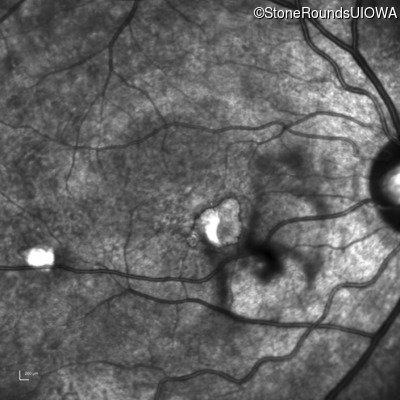

Infrared Fundus Photograph - Right - 20/40 -1

Exemplar

Infrared Fundus Photograph - Left - 20/20 -2